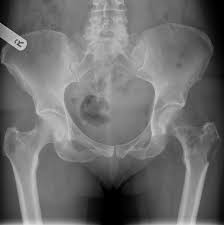

Learn about bone cancer symptoms and treatments. The national cancer institute explains that pain and swelling in the hip are common symptoms of bone cancer. Any bone can be affected, although bone cancer most often develops in the long bones of the legs or upper arms. Bone cancer can start in any of the many bones of the body; Even though swelling can occur with bone cancer in the hip, swelling is often the symptom of something else. What are the types of bone cancer? It most commonly affects the hips (pelvis) and long bones in the leg. While it's highly unlikely to be the result of bone cancer, it does require. You should seek medical care if you have a new pain in your bones that does not resolve or worsens over time, if you have a sudden and more severe pain in your. Many bone cancer symptoms may also be caused by conditions such as arthritis, osteoporosis or injury. Most bone cancers are not hereditary. Primary bone cancer is a rare type of cancer that begins in the bones. In rare cases, these can also.

Chordoma Is The Most Common Malignant Primary Bone Cancer In The Adult Spine from www.spineuniverse.com Read about bone cancer prognosis, treatment, symptoms, signs, survival rate, types, metastatic, and stage 4. Cancer in bone can cause intermittent or progressively severe localized bone pain where the cancer is in the bone. What is the most important thing in an emergency? Bone cancer develops in the skeletal system and destroys tissue. The national cancer institute explains that pain and swelling in the hip are common symptoms of bone cancer. Osteochondroma is the most common. This type of cancer rarely occurs in people under 20 and is. It can spread to distant organs, such as the lungs.

Hip Pain And Cancer Why Your Hip Pain May Or May Not Be Cancer from post.healthline.com While cancer metastases in the bone marrow for malignant tumors of the colon occur only in 8% of cases. The most common symptom of bone cancer in the hip is hip pain, which can be severe enough to disrupt what are the signs and symptoms of primary bone cancer? What is the most important thing in an emergency? Do you know what bone cancer symptoms look like? Bone pain can cause a dull or deep ache in a bone or bone region (e.g., back, hips, legs, ribs, arms). Read about bone cancer symptoms with bone pain. It forms in cartilage cells, usually in flat bones such as the blade, hip, or pelvis. What are bone cancer symptoms and signs?

Any bone can be affected, although bone cancer most often develops in the long bones of the legs or upper arms. Learn more about the symptoms, risk factors, diagnosis, types, treatment, and outlook for bone cancer. Osteochondroma is the most common. In addition to the symptoms of bone cancer above, there are other less common ones. What are bone cancer symptoms and signs? Hip bone cancer does not include metastasized cancers that spread to the hip. The most common symptom of bone cancer is pain, which is caused by either the spread of the tumor or the breaking of bone that is weakened by a tumor. A dull, aching pain in the groin, outer thigh, knee. Cancer in bone can cause intermittent or progressively severe localized bone pain where the cancer is in the bone. There are two kinds of fracture: 1 watching for symptoms of bone cancer. The break may occur in an area of the bone that had previously been sore or painful for a. Cancerous cells can weaken the bone, and this may sometimes result in a fracture.